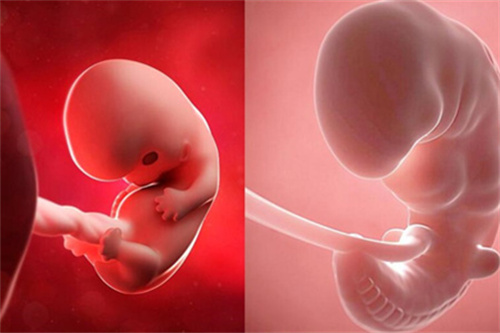

孕期